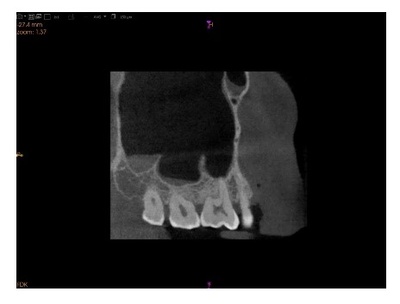

Cone-Beam Computed Tomographic Evaluation of Maxillary Sinus Anatomy and Septal Variations: Clinical Implications for Surgical Safety

Written by Rithanya Prabakaran   Published on Issue 4 Vol 13, 2025

Comprehending the architecture of maxillary sinus and its septa is crucial for preventing complications during maxillofacial procedures, as it guides clinicians in selecting optimal surgical techniques. This study used cone-beam computed tomography (CBCT) to examine anatomical variations of maxillary sinus and its septa. CBCT scans of 500 dentate patients aged 25–65 years who underwent head and neck imaging at Department of Radiology, Saveetha Dental College and Hospitals, Chennai, India, betwee